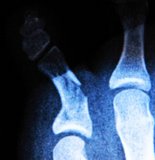

骨折

By Erik Charlton (CC)

たとえば骨折がテーマだとする。難しい訳語の例として「 Reduction 」を取り上げてみよう。Reduction自体は「 減らすこと 」、「 減少 」だということは高校生でも分かるだろうけど、これでは骨折をテーマとした医療文献では意味をなさない。医療、臨床の場面では 「 整骨 」、「 整復法 」が正しい訳語なのだが、前者は昔の言い方で、今では後者の方がより望ましい。

続けて、同じ骨折を整復するにしても、「 open 」と「 close 」がある。オープンとクローズなら小学生でも意味は分かると思うけれど、これを医療専門用語で訳するのが難しい。Openの方は 「 傷口を開いて 」 治すのだから外科的処置をともなう治療という状況は思い浮かぶが、この言葉の正しい訳は 「 観血的整復法 」 となる。

「 観血的 」。医療に特に関わる必要性が無ければ、おそらく一生にいちども使わない語彙ではないだろうか。「 血を観る 」から観血的。つまりは漢語なのだ。ちなみに、closed reduction の訳は「 徒手整復 」。これは、昔ながらの骨接ぎのように、外科的でない治療というのは人間の手による治療だからだろう。「 手でもって 」(=つまり「手で」)治すから徒手。